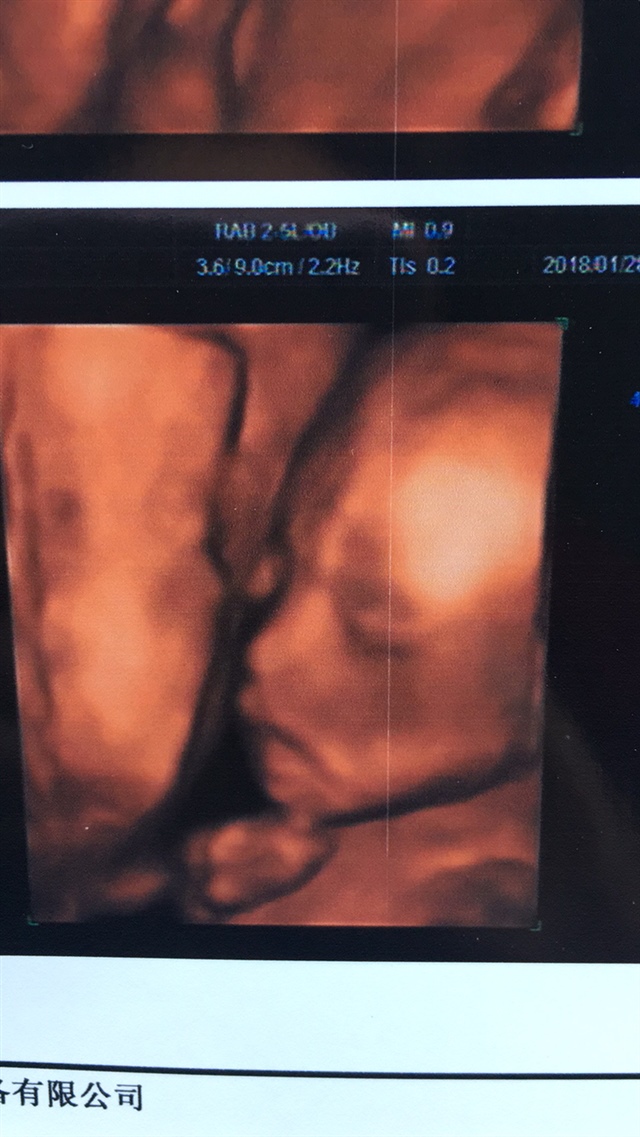

孕20周+1天

🌷🌸Ms.董🦄🍬[帖主]:都说是男孩

金晨:你做过四维彩超,他们应该暗示你性别了吧?

宝宝允吸自己手手的图片太可爱了,好神奇。